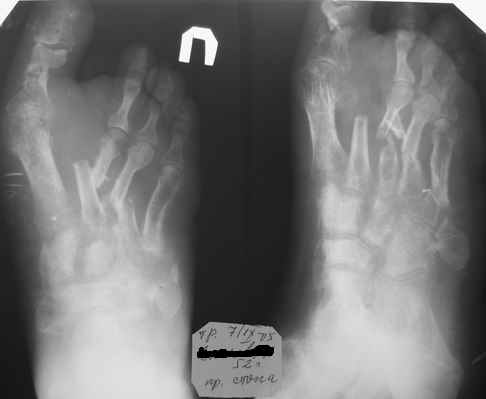

Здравствуйте, Тимур Вячеславович. Спасибо за живой интерес к проблеме: этапы к Вам понял. Насчет ампутации, я думаю, что больной еще не созрел, наоборот- полон оптимизма. Вот свежие рентгенограммы и стопа на 5 день после операции. Появились грануляции, но рана глубокая- 2-2,5 см. Хотелось бы узнать о Вашей тактике на ближайший период, если это возможно. С уважением, Алексей

Здравствуйте, Алексей. А на самом деле все не так уж и плохо. По моему сейчас нужно купировать воспалительный процесс, добиться заживления раны а затем думать о реконструктивной операции. а пока, после появления обильных грануляций ванночки со слабым раствором марганцовки (3-4 кристаллика) до полной готовности кожных покровов (каждый день по 2-3 раза).

Говорить об оперативном вмешательстве можно будет только после полного стихания воспалительного процесса. А это около года. О какой операции говорить после года после травмы? Сейчас сложно говорить. Мне кажется необходимо дождаться стихания воспаления, провести разработку суставов, "расходить" ногу, а потом уже смотреть, что из этого вышло. Нужно-ли оперировать и добиваться идеальных снимков в этом случае? Сомневаюсь.